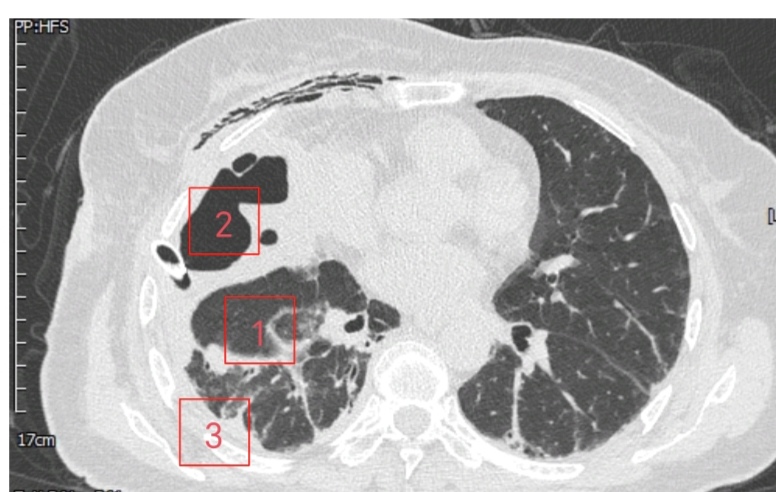

患者是一位61岁女性,诊断右侧巨型肺大疱已2年,近1周突发不明原因高热伴胸痛,体温最高达39.0℃。就诊于清华大学附属垂杨柳医院急诊科。经胸部CT检查,提示右侧巨型肺大疱(最大直径约15cm)内出现液平(最大直径约10cm),考虑疱内感染。虽经规范内科抗感染治疗,高热、胸痛症状未显著缓解,且进行性加重至无法脱离氧气支持,遂紧急转入我科进一步诊治。在胸外科主任崔健指导下,胸外科医师赵洋乐即刻联系超声科,在其精准引导下实施右侧肺大疱内及右侧胸腔脓液闭式引流术,成功引流出超过1000ml坏死液体。术后患者体温迅速恢复正常,胸痛显著缓解,脱氧状态下可自如活动。然病灶尚未根除,鉴于患者既往肺功能低下且近期高热导致营养状况不佳,需先行呼吸功能锻炼与全面营养支持,再择期手术。术前评估时,崔健围绕患者手术潜在风险,表示:1.胸腔内广泛粘连可能导致腔镜操作困难,需中转开胸;2.术中大面积渗血引发血压剧烈波动;3.肺大疱基底范围过大致无法彻底根治性切除;4.术中感染控制不佳可能引发术后严重胸腔感染及伤口不愈;5.肺功能低下致术后脱机困难。

经充分术前准备,胸外科医疗团队为患者行经胸腔镜右侧肺大疱切除术+经胸腔镜胸膜粘连松解术+经胸腔镜脓胸清除术。手术历时约4小时。术中,麻醉科医师凭借丰富经验为手术平稳保驾护航,崔健以精细操作成功规避中转开胸。术中及术后感染的有效防控也避免了胸腔感染及伤口愈合不良的发生,患者最终顺利康复出院。这场对抗复杂肺部疾病的战役中,患者最终成功重获健康,这既得益于胸外科崔健与胸外科医疗团队的精湛治疗与悉心调理,更离不开麻醉科、超声科、放射科及急诊科等兄弟科室的鼎力协作。多学科团队的强力支持,赋予胸外科迎战任何挑战的坚定信心。

▲术后1周胸部CT纵膈窗/肺窗

▲术后1月胸部CT纵膈窗/肺窗